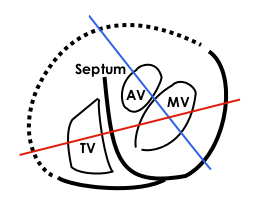

Base of ventricles exposed by removal of the atria. (Bicuspid (mitral) valve visible at bottom left.) | |

Section of the heart showing the ventricular septum. (Bicuspid valve visible at center.)

Section of the heart showing the ventricular septum. (Bicuspid valve visible at center.)

Apical view of valves

Apical view of valves Cross-sectional view of mitral valve between left atrium (upper chamber) and left ventricle (lower chamber), which shows parts of walls of left atrium and left ventricle that are next to the mitral valve.